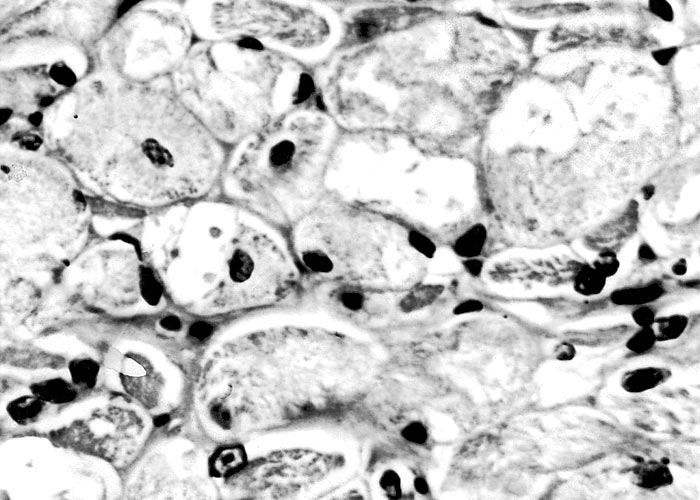

The most complete account of the lesions in vermeersiekte is given by Pienaar et al.113 (1973), who described changes in both the skeletal muscles and oesophagus. Light microscopical examination revealed lesions in randomly distributed individual myocytes or groups of muscle fibres. Affected fibres contained vacuoles of different size into which one or more sarcolemmal nuclei had often intruded (Figures 12 and 13). The sarcoplasm surrounding these vacuoles was in some instances hyalinized (Figure 14). In more chronic experimental cases, the size of the muscle fibres varied, some of the hyalinized fibres being smaller and showing proliferation and centralization of sarcolemmal nuclei. Ultramicroscopical studies showed that the vacuoles in the sarcoplasm were caused by the degeneration of myofibrils in otherwise intact-muscle fibres. The thick myofibrils were first to disappear, resulting in a loss of the A-band (Figure 15), followed by shredding of the remaining filaments, until ultimately all the myofibrils were destroyed (Figure 16). Fine granular material, containing remnants of myofilaments, Z-band material (Figure 16) and swollen vacuolated mitochondria, were evident in such fibres. As a result of the loss in myofibrils the diameter of some of the muscle fibres was reduced.113